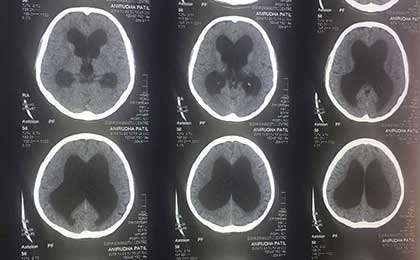

Arrested Hydrocephalus CT